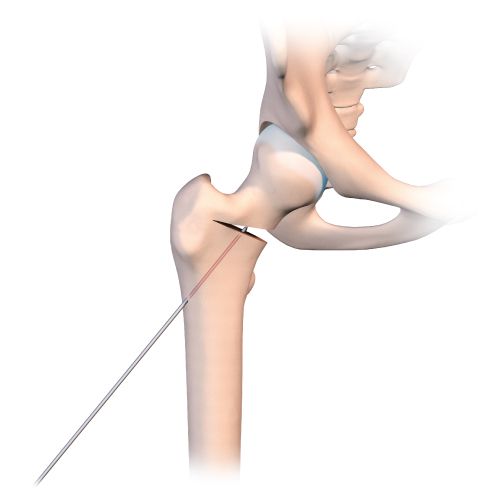

Just before using the orthopaedic table to begin the compression, it is a good idea to use a tibial drill guide (as for cruciate ligament repair) (Figs. 2b, c, d).

This makes it much easier to guide a pin into the osteotomy line that has just been created. The pin should of course sit just within the osteotomy line, without going any further. Applying compression will close the line and fix the pin in the neck and head of femur. With the osteotomy line closed and the pin in place, the final stage is to insert a 7mm cannulated screw to stabilize the fixation. A second or even third screw may be used if necessary. The image intensifier should be used to check the correct placement of the screws (Fig. 2e).